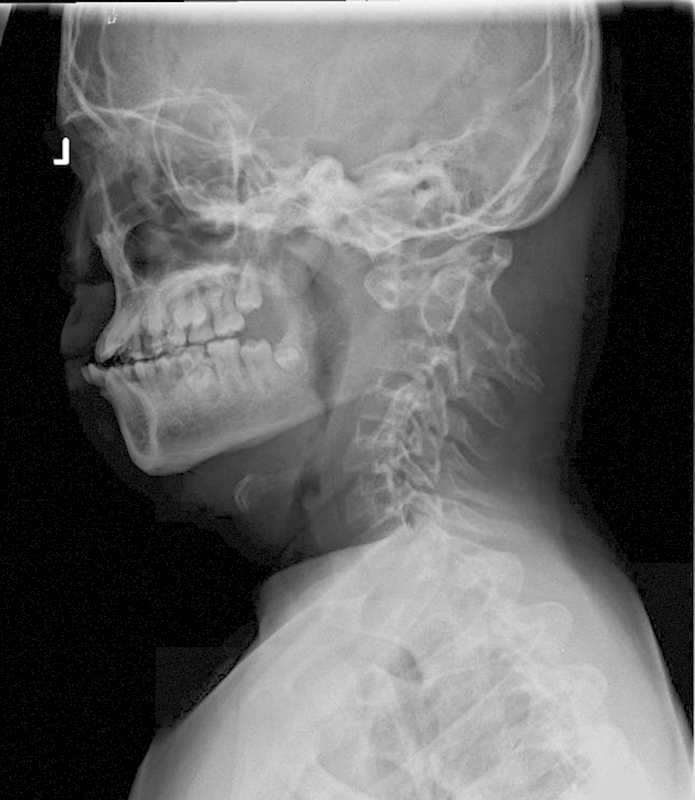

Study Design Retrospective case review. Objective Atlantoaxial instability with and without basilar invagination poses a considerable challenge in management regarding reduction, surgical approach, decompression, instrumentation choice, and extent of fusion. A variety of strategies have been described to reduce and stabilize cranial settling with basilar invagination. Modern instrumentation options included extension to the occiput, C1-C2 transarticular fixation, and C1 lateral mass-C2 pars among others. Since not all cases of cranial settling are the same, their treatment strategies also differ. Factors such as local vascular anatomy, amount of subluxation, need for distraction, and shape of occipital condyles will dictate level and type of instrumentation. The objective of this study was to outline treatment options and provide a rationale for the surgical plan. Methods Two cases of C1-C2 instability in patients with Down syndrome are described. Case 2 underwent C1-C2 instrumented fusion, whereas case 1 involved posterior instrumented fusion to the occiput. Results Both patients tolerated the procedures well. There were no complications. Minimum follow-up was 1 year. There was no loss of reduction. Solid arthrodesis was achieved in both cases. Conclusion Successful reduction can be achieved with both C1-C2 instrumented fusion as well as O-C instrument fusion. Factors such as local vascular anatomy, amount of subluxation, need for distraction, and shape of occipital condyles will dictate level and type of instrumentation.